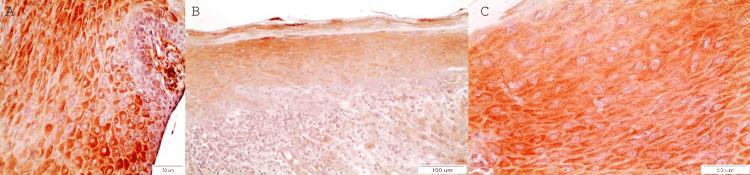

DAPK-1在口腔白斑和口腔鳞状细胞癌中的免疫组化表达:一项初步研究

The silencing of death-associated protein kinase 1 (DAPK-1) is an effective way of inactivating a tumor-suppressing mechanism. The aim of this study was to investigate the immunohistochemical expression of DAPK-1 in oral leukoplakia (OL) and oral squamous cell carcinoma (OSCC).

DAPK-1 IHC expression was increased in OLs without dysplasia and with OLs with mild dysplasia compared to moderate/severe dysplasia (p=0.019, Mann-Whitney U Test) and OSCCs (p=0.003, Mann-Whitney U Test).  Conclusions: DAPK-1 seemed to function as an oncosuppressor molecular biomarker, as its expression was decreased in areas of cellular dysplasia in OLs and in areas of OSCCs composed of less differentiated cells. The clinical application of this biomarker is that the positively stained, potentially malignant lesions are less likely to transition into malignancy, and cancerous lesions are more likely to behave non-aggressively. On the other hand, the lack of staining could signify the loss of this oncosuppressing ability, and it could be a potential prognostic biomarker for OSCC's aggressive biologic behavior if considered with other clinical parameters and a prognostic factor of malignant transformation of potentially malignant lesions. Since this is a preliminary study, more studies with larger sample sizes are required to support these conclusions.

死亡相关蛋白激酶1(DAPK-1)的沉默是使肿瘤抑制机制失活的一种有效方式。本研究的目的是调查DAPK-1在口腔白斑(OL)和口腔鳞状细胞癌(OSCC)中的免疫组化表达情况。

与中度/重度发育异常的OL和OSCC相比,DAPK-1的IHC表达在无发育异常的OL和轻度发育异常的OL中有所增加(曼-惠特尼U检验,p = 0.019)以及在OSCC中(曼-惠特尼U检验,p = 0.003)。结论:DAPK-1似乎作为一种肿瘤抑制分子生物标志物发挥作用,因为其在OL的细胞发育异常区域以及由分化程度较低的细胞组成的OSCC区域中表达降低。这种生物标志物的临床应用在于,阳性染色的潜在恶性病变转变为恶性的可能性较小,而癌性病变的侵袭性可能较低。另一方面,缺乏染色可能表明这种肿瘤抑制能力的丧失,如果与其他临床参数一起考虑,它可能是OSCC侵袭性生物学行为的潜在预后生物标志物,也是潜在恶性病变恶性转化的预后因素。由于这是一项初步研究,需要更多样本量更大的研究来支持这些结论。